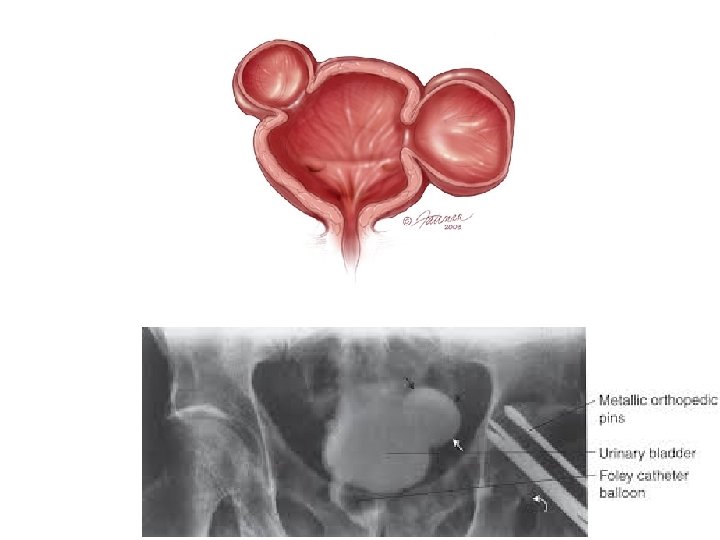

Močový měchýř (Vesica urinaria, Urokystis) • apex, corpus, fundus, cervix, uvula, (vertex) • trigonum vesicae • svaly: hladké – m. detrusor (parasympatikus) – m. trigoni vesicae – ♂m. sphincter vesicae (sympatikus) • projekce: za symphysis pubica (u dětí nad)

Trigonum vesicae Lieutaudi • ostia ureterum (2) • ostium urethrae internum • kraniálně: plica interureterica Mercieri – fossa retrotrigonalis • laterokaudálně: Bellovy snopce • chybějí řasy • podklad původem z Wolffova vývodu

Močový měchýř • sliznice složena v řasy kromě oblasti trigonum vesicae • plica ureterica se táhne laterálně nad ostium ureteris • hladká svalovina tvoří 3 nepřesně oddělitelné vrstvy: – vnitřní síťovitá (plexiformní) až podélná – střední kruhová ( m. sphincter vesicae pouze u mužů !) – vnější podélná • seróza (peritoneum) pokrývá: – horní plochu měchýře u ženy – horní a část zadní u ženy

Cystografie